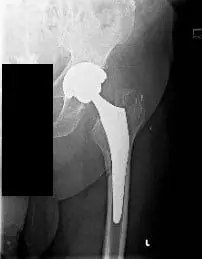

Preoperative X-ray of the Left Hip AP view showing a periprosthetic femoral fracture (minimally displaced along the medial aspect of the proximal femoral shaft) with subsidence of the stem

Preoperative X-ray of the Left Hip AP view showing a periprosthetic femoral fracture (minimally displaced along the medial aspect of the proximal femoral shaft) with subsidence of the stem.